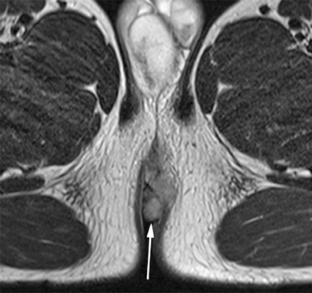

Perianal complications of Crohn disease are a common occurrence in children and can result in significant morbidity when not accurately characterized prior to surgical intervention. MRI is an excellent imaging modality for the evaluation of perianal inflammatory bowel disease – allowing characterization and detailed description of perianal fistulas. MRI has many advantages over other imaging modalities for the pediatric patient. Radiologists will benefit from a sophisticated understanding of perianal anatomy, the classification of perianal fistulas, the advantages MRI offers in characterization of perianal fistulas as well as the common and incidental findings that are important in the MRI evaluation of perianal inflammatory bowel disease in children. Perianal fistulas are found at a high rate in pediatric referrals and are more commonly found in male patients.

Fig. 1